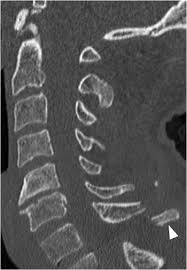

A transverse process fracture at the level of l5 is a surrogate marker of vertical instability of the pelvic fracture due to the attachment of the iliolumbar ligaments. Possible causes, signs and symptoms, standard treatment options and means of care and support. Transverse processes are used as lever arms by the deep spinal muscles to maintain posture and to induce rotation and lateral bending. It may occur as an avulsion fracture due to strong contracture of the muscles. Although the fracture is not associated with spinal cord damage and neurological deficits, the extreme force of the injury can cause visceral injuries and internal hemorrhage. The presence of other injuries might also be assessed due to the level of force needed to break the transverse process. In 78% of transverse process fractures, ct scanning showed that the fracture extended into the transverse foramen. Transverse process fractures caused by stress are likely under detected since even an acute transverse process fracture requires a high index of suspicion to be correctly identified(4,7). Here is an example of a patient with a benign looking transverse process fracture with an associated significant injury to the back. Transverse process fracture you have fractured a transverse process. Thoracic transverse process fractures (ttpfs) are injuries that go unnoticed during traditional autopsies, as demonstrated by a lack of medicolegal publications regarding ttpfs. We retrospectively reviewed the reports of lumbar spine and abdominopelvic ct scans from 2017 and 2018 to classify the types of spine fractures, their mechanism of injury, treatment and. Up to 60% of lumbar transverse process fractures identified on ct will be missed on plain radiographs.

The transverse foramen is an opening on each of the transverse processes of the cervical spine which gives passage to the vertebral artery and vein and a sympathetic nerve plexus. There are two transverse processes that extend off each vertebra in the details: Transverse process fractures are common sequelae of trauma, although they are considered a minor and stable lumbar spine fracture. Transverse processes are typically fractured in direct blows from athletics touch or impact from falls from bikes/motorbikes or by heights. However, postmortem computed tomography (pmct) has made detection of this type of injury easy. There are two transverse processes that extend off each vertebra in the spine, one on each side. A transverse process fracture is a break in 1 or more transverse process. In 78% of transverse process fractures, ct scanning showed that the fracture extended into the transverse foramen. A transverse process fracture is considered as a rare injury. A transverse process fracture is a break in 1 or more transverse process. What is a transverse process fracture? Transverse process fractures caused by stress are likely under detected since even an acute transverse process fracture requires a high index of suspicion to be correctly identified(4,7). If ct confirms isolated injury lateral flexion/extension views are indicated to rule out dynamic instability.

However, postmortem computed tomography (pmct) has made detection of this type of injury easy. There are two transverse processes that extend off each vertebra in the details: What is a transverse process fracture? It may occur as an avulsion fracture due to strong contracture of the muscles. It occurs as a result of sudden and extreme trauma. If ct confirms isolated injury lateral flexion/extension views are indicated to rule out dynamic instability. Vertebral angiography, performed in eight patients with fractures involving the transverse foramen, showed dissection or occlusion of the vertebral artery in seven (88%) instances. This part extends out from the side of the main body of the bone (called the vertebral body). A transverse process fracture at the level of l5 is a surrogate marker of vertical instability of the pelvic fracture due to the attachment of the iliolumbar ligaments. We retrospectively reviewed the reports of lumbar spine and abdominopelvic ct scans from 2017 and 2018 to classify the types of spine fractures, their mechanism of injury, treatment and. Up to 60% of lumbar transverse process fractures identified on ct will be missed on plain radiographs. In 78% of transverse process fractures, ct scanning showed that the fracture extended into the transverse foramen. Transverse process fractures identified on helical computed tomography (ct) scans without the presence of any other fracture or.